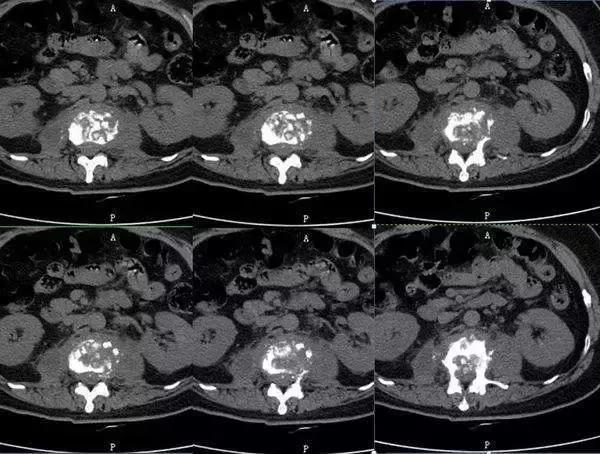

2.CT 对密度的识别非常高,可以对脊柱椎体、附件等生理结构及被感染破坏后的椎体结构即骨质破坏情况、骨质增生情况、骨质硬化改变的情况、骨质病变的范围等清晰显示,可较有效的对椎体骨质的破坏程度进行评价。